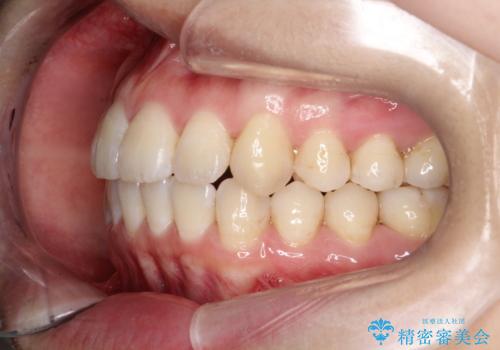

【インビザライン】前歯の凸凹をなおしたい

- 前歯の凸凹をなおしたいことを主訴にインビザラインにて矯正治療を行いました。

患者様にしっかりとインビザラインを使用して頂けたことで綺麗な仕上がりとなりました。